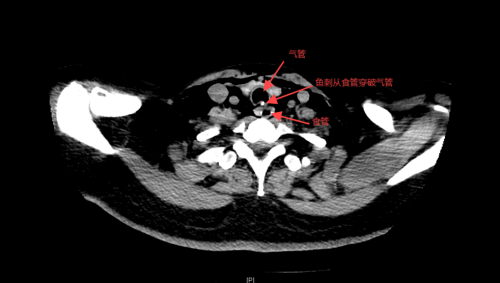

接诊的急诊科副主任、主任医师赫留党详细询问了她的经历,完善体查,发现李小华颈部及胸壁局部肿胀,考虑吞食异物导致食管破裂的可能,立马陪同患者完善了颈部及胸部CT,结果证实了之前的判断,影像学提示颈段食管异物,并气管、食管局部破裂,颈部皮下、纵膈及前胸部多发气肿。

耳鼻咽喉头颈外科团队紧急参与会诊,随后患者转入耳鼻咽喉头颈外科,完善术前准备后在全麻下行食管瘘修补+食管异物取出术。术中取出一根长约3厘米的条状粗大鱼刺。参与手术的耳鼻咽喉头颈外科副主任医师康晓明分析,李女士鱼刺卡喉后采取错误的方法吞咽饭团,致使鱼刺进一步扎入食管深处,随后穿透食管、气管后壁,引发食管气管瘘。所幸急诊科及耳鼻喉科医护团队联手救治,迅速作出准确的判断和决策,让患者转危为安。